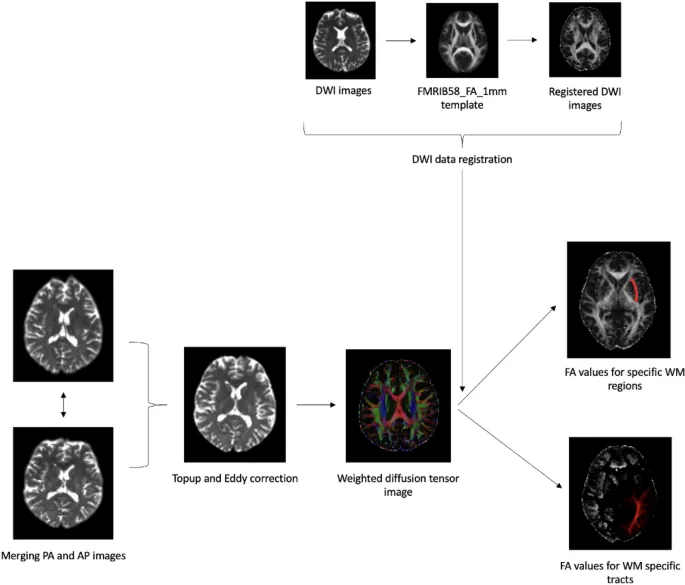

Методология исследования

В исследовании приняли участие 22 человека без опыта в стратегических играх, которые прошли 30-часовое обучение игре StarCraft II. Перед началом тренировок всем участникам провели диффузионную магнитно-резонансную томографию (дМРТ) для оценки целостности белого вещества мозга.

Результаты показали значительную корреляцию между целостностью белого вещества и успехами в игре. Более высокая фракционная анизотропия (показатель целостности белого вещества) в правой части поясной извилины/гиппокампа была связана с лучшими показателями APM и меньшей задержкой PAC.

Нейронные корреляты

Целостность белого вещества в правой передней ножке внутренней капсулы положительно коррелировала с использованием горячих клавиш. Также была обнаружена связь между FA в левом нижнем продольном пучке и игровыми показателями.